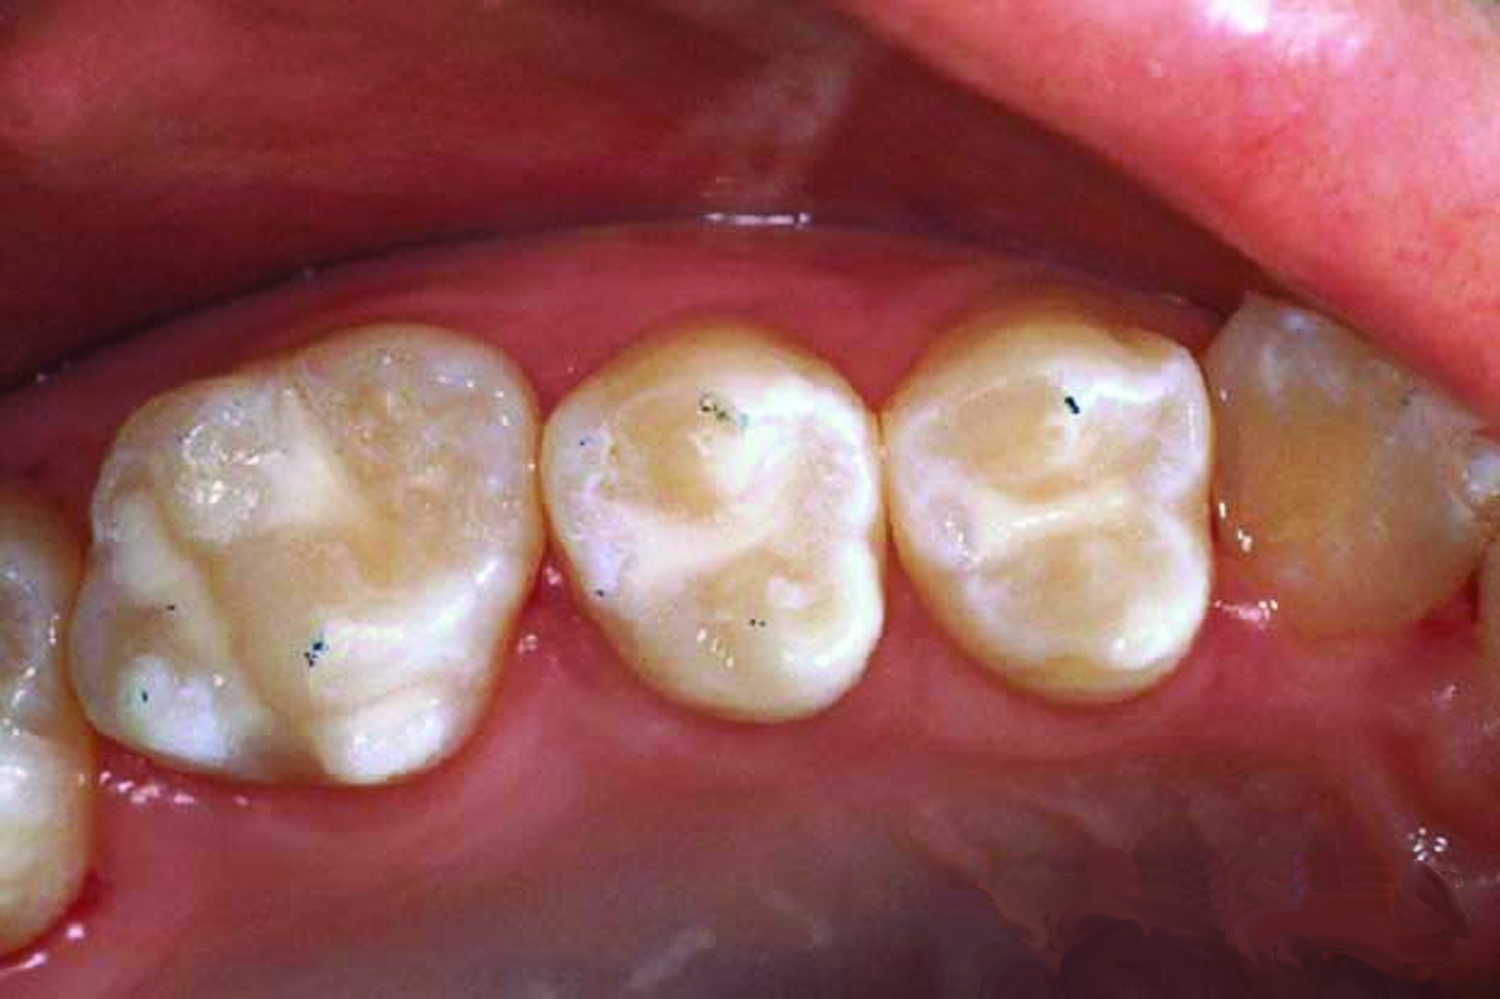

8. Dry the tooth surface with compressed air for a minimum of 10 seconds. A properly etched surface will appear white, dull, and frosty (Figure 9).

Fig 9. Dry the tooth surface again with compressed air for a minimum of 10 seconds. A properly etched surface appears white, dull, and frosty.

Figure 9